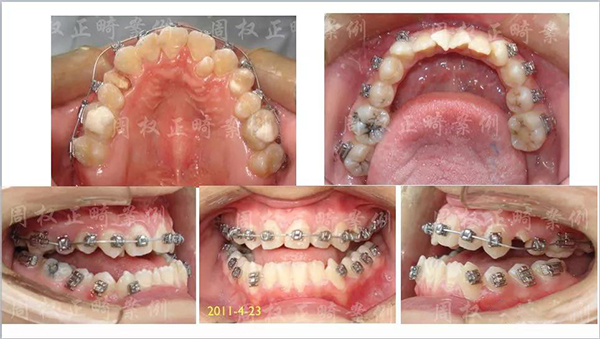

具体的看治疗过程:

第一次初诊时的资料

粘矫治器

矫正初期下前牙不粘矫治器是重点

矫正后尖牙磨牙咬合关系建立了一类咬合!

下颌第三磨牙咬合有所欠缺!